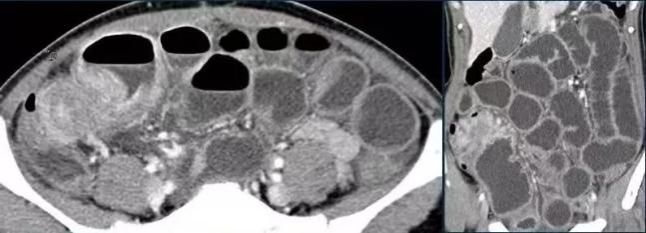

可领奖的开心劲儿还没过,身体先扛不住了。一开始只是肚子胀、总想上厕所,到了夜里,腹痛突然加重,恶心、干呕,却什么也吐不出来,整个人疼得直不起腰。家人将他紧急送医,经腹部CT检查,确诊为急性机械性小肠梗阻,罪魁祸首,正是短时间内过量食用胡萝卜丝。

2.肠梗阻

像李先生那样,大量高纤维食物(胡萝卜、海带、芹菜、土豆等)短时间内涌入肠道,会在肠道内堆积、吸水膨胀,形成“食团”堵塞肠腔。肠腔内压力持续升高,肠壁血液循环受阻,可导致肠坏死、穿孔,甚至感染性休克。